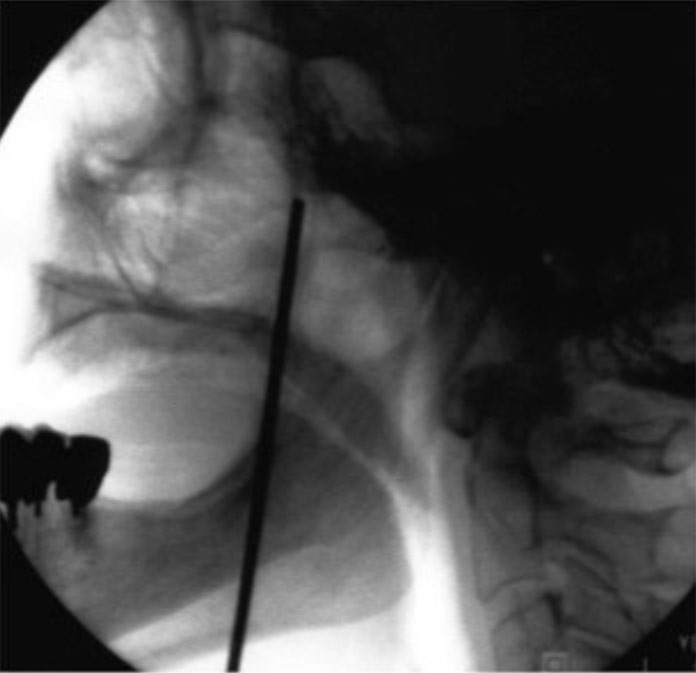

Radiofrecuencia-del-ganglio-esfenopalatino-p